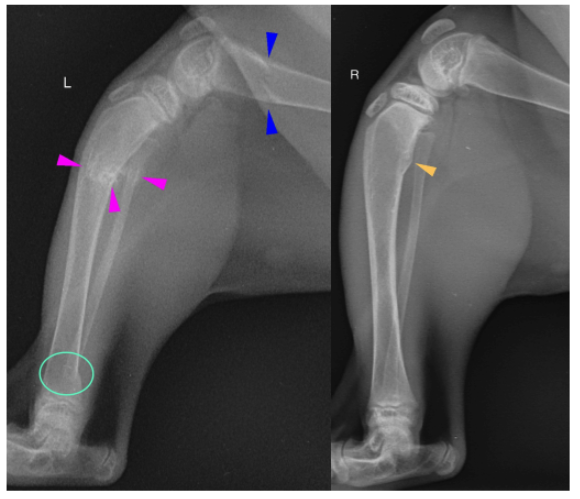

The femoral cortices are thin as compared to the tibial cortices. There are oblique folding fractures in the left distal femoral metaphysis (dark blue arrowheads) and left tibial and fibular proximal diaphyses (light pink arrowheads). Faint periosteal proliferation surrounds the fracture margins of the tibial and fibular fracture sites. The distal femoral segment is mildly cranially angulated with cranial angulation of the proximal tibial segment. There is a stair-step like lesion in the left tibial distal diaphyses (light mint circle) in the caudal cortex, as compared to the right.

The right tibial proximal metaphyseal caudal cortex is bulging caudally with smooth increased periosteal proliferation (tan arrowhead).

The left talar ridges are sclerotic and the margins are ill-defined from the distal tibial epiphysis on the lateral image, as compared to the right. The right and left calcanei are lucent within the body, with an ill-defined trabecular pattern and the cortices are thin.

The right hind soft tissues are thicker than the left cranially, however, the right limb is more flexed than the left.